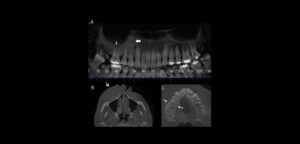

La evaluación correcta de la condición del hueso periodontal es esencial para el diagnóstico, planificación, tratamiento y el pronóstico de la enfermedad periodontal, en conjunto